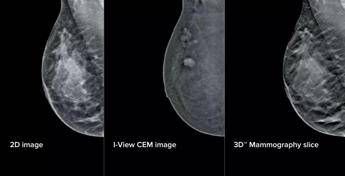

(Adnkronos) – All'azienda ospedaliera San Camillo-Forlanini di Roma la mammografia diventa 'intelligente'. Grazie all'integrazione di intelligenza artificiale e mammografi di ultima generazione, la Uosd Diagnostica per immagini in senologia ha messo a punto "un intervento tecnologico profondo che coinvolge strumenti, software e flussi di lavoro, ottimizzando l'attività dei professionisti e rendendo i percorsi diagnostici più semplici e meno gravosi" per le pazienti, spiega l'Ao in una nota. La Breast Unit dell'ospedale romano, si legge, "risulta ad oggi l'unica struttura pubblica in Italia a vantare una configurazione così completa e all'avanguardia per quanto riguarda i mammografi del segmento". L'aggiornamento – illustra il San Camillo – si compone di elementi fisici e virtuali in due ambiti principali: la mammografia con refertazione e la biopsia mammaria. Sul fronte della refertazione, è stata introdotta una nuova workstation con monitor ad altissima risoluzione e strumenti avanzati di analisi delle immagini. Un software dedicato consente di valutare in modo oggettivo la densità del tessuto mammario, un elemento importante perché associato al rischio di tumore al seno. A questo si aggiunge un software che analizza struttura e densità del tessuto mammario, tecnologia di tomosintesi avanzata che riduce del 66% il numero di slice – le 'fettine' spesse 1 mm di tessuto mammario acquisite dal mammografo – mantenendo le stesse informazioni diagnostiche. Meno immagini da scorrere significa meno affaticamento: una riduzione del carico cognitivo per il radiologo stimata intorno al 13%, con benefici concreti soprattutto nelle sessioni di lettura multipla. A supporto dei medici – prosegue la nota – è stato integrato anche un sistema di intelligenza artificiale che evidenzia automaticamente le aree sospette sulle singole slice, come microcalcificazioni o alterazioni del tessuto, e fornisce indicazioni utili per la priorità di lettura. Studi preliminari indicano "un miglioramento della capacità di individuare lesioni fino al 9%". Sul fronte della biopsia mammaria, i mammografi di ultima generazione consentono di eseguire la procedura direttamente a partire da immagini con contrasto, unendo in un unico passaggio la localizzazione della lesione e il prelievo bioptico. Per la paziente questo si traduce in un percorso interamente nello stesso reparto, senza la necessità di ricorrere alla risonanza magnetica chiusa. Un apposito dispositivo meccanico permette inoltre di raggiungere anche le lesioni in posizioni difficili. "Come ingegneri clinici, ci impegniamo a garantire che la tecnologia a servizio della medicina sia costantemente appropriata e all'avanguardia – afferma Annarita Caporaso, direttore Uoc Ingegneria clinica – Nel progetto in questione ci siamo posti l'obiettivo di coadiuvare l'occhio e l'esperienza del medico con un'architettura tecnologica capace di potenziarne le capacità analitiche. Attraverso algoritmi di intelligenza artificiale studiati per migliorare la qualità diagnostica a supporto della valutazione clinica, l'innovazione diventa uno strumento concreto al servizio della diagnosi. Non si tratta solo di potenza di calcolo, ma di un'autentica efficienza dei processi: riducendo drasticamente il volume di dati da analizzare, migliorando così il flusso di lavoro. Abbiamo messo a punto un'infrastruttura solida che garantisce la massima sicurezza clinica e trasforma l'innovazione in un percorso diagnostico fluido, preciso e ultramoderno". Aggiunge Francesca Svegliati, responsabile Uosd Diagnostica per immagini in senologia: "Oggi abbiamo strumenti che ci permettono di essere ancora più precisi, individuando dettagli e microcalcificazioni difficili da rilevare a occhio nudo. Questo rafforza la sicurezza diagnostica e ci consente di offrire risposte più rapide. L'upgrade più importante riguarda le biopsie guidate con mezzo di contrasto (Cem): poter sottoporre a biopsia lesioni non altrimenti evidenziabili o visibili solo in risonanza magnetica ci consente di raggiungere una precisione nella stadiazione locale già in reparto senza ricorrere a procedure diagnostiche – biopsia Rm guidata – che risultano molto più impattanti sul percorso della paziente. Per chi si rivolge a noi significa meno attesa e meno tensione, con un percorso più fluido, semplice e accurato".